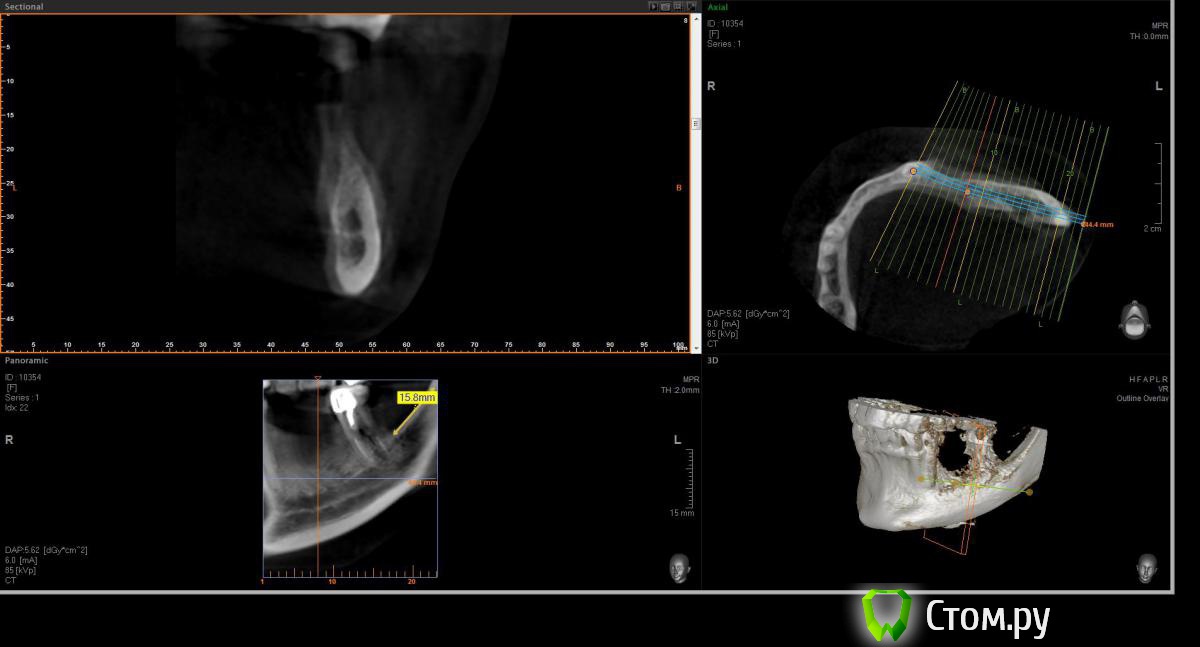

Opimar Опубликовано 21 июня, 2014 Поделиться Опубликовано 21 июня, 2014 Здравствуйте коллеги. Прошу вашей помощи и совета с пациенктой. В анамнезе травматичное удаление около 2-3 лет назад 35-36. Со слов пацинтки удалялось долотом и в 2 приема, вообщем по прошествию времени результат плачевный К мостовидному протезу пациентка не готова, очень хочет лечение с имплантантами и готова к костной пластике. Восстановить такой дефект ,если я правильно понимаю, более-менее прогнозируемо можно только с трансплантацией аутокостных блоков. Как раз по типу того как выкладывал Mane http://forum.stom.ru/topic/25799-kk-monokortikalnye-bloki/ либо по Кюри. Сам склоняюсь к забору блока с наружной косой линии или с подбородка. С блоками работать буду первый раз. Прослушал курсы Томаса Хансера. Прошу высазать идеи и предложения,возможны ли альтернативные методы? Кт прилагаю. Спасибо Ссылка на комментарий

Opimar Опубликовано 21 июня, 2014 Автор Поделиться Опубликовано 21 июня, 2014 Выкладываю еще. Пошагово от 34-37 Ссылка на комментарий

Bier Опубликовано 21 июня, 2014 Поделиться Опубликовано 21 июня, 2014 Выкладываю еще. Пошагово от 34-37темная точка достаточно высоко, это по моему не нерв, нерв ниже, я правильно понимаю? Ссылка на комментарий

Opimar Опубликовано 21 июня, 2014 Автор Поделиться Опубликовано 21 июня, 2014 темная точка достаточно высоко, это по моему не нерв, нерв ниже, я правильно понимаю?Да он ниже и язычнее. Провел от менталиса там еще запас есть. Ссылка на комментарий